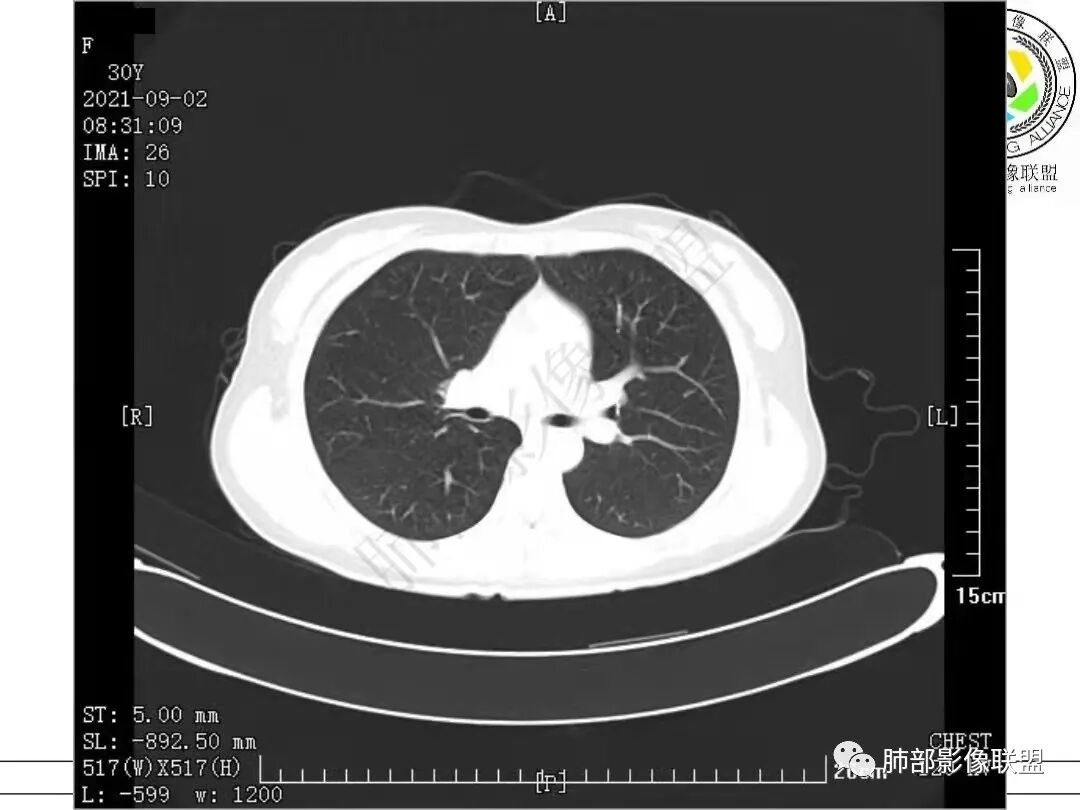

病例一

1.病例一:68岁男性,体检发现肺结节,肿瘤标志物CA199、CA50、CEA升高,其中CEA升高显著,超过正常范围的5倍以上。右肺下叶胸膜下结节影,整体较膨隆,部分层面可见锯齿状边缘,边界清晰,周围可见细毛细影,可见血管集束征、胸膜牵拉。密度不均,可见磨玻璃密度区及空泡征,胸膜下脂肪间隙显示不清。增强后显示轻、中度强化。

病例一讨论

老年男性,肿瘤标志物高,右肺下叶结节,边缘可见短毛刺及胸膜牵拉,期内可见空泡,不均匀强化,考虑浸润性腺癌。

晨读 老年男性,肿标高。右肺下叶胸膜下结节影,轻度分叶,短毛刺,支气管截断,病灶内密度不均空泡形成,胸膜牵拉。考虑腺癌可能大,隐球菌待排。

晨读,老年男性,cea,ca199升高,右肺结节,有毛刺,分叶,空泡征,胸膜凹陷,血管集束,考虑肺腺癌,鉴别隐球菌。